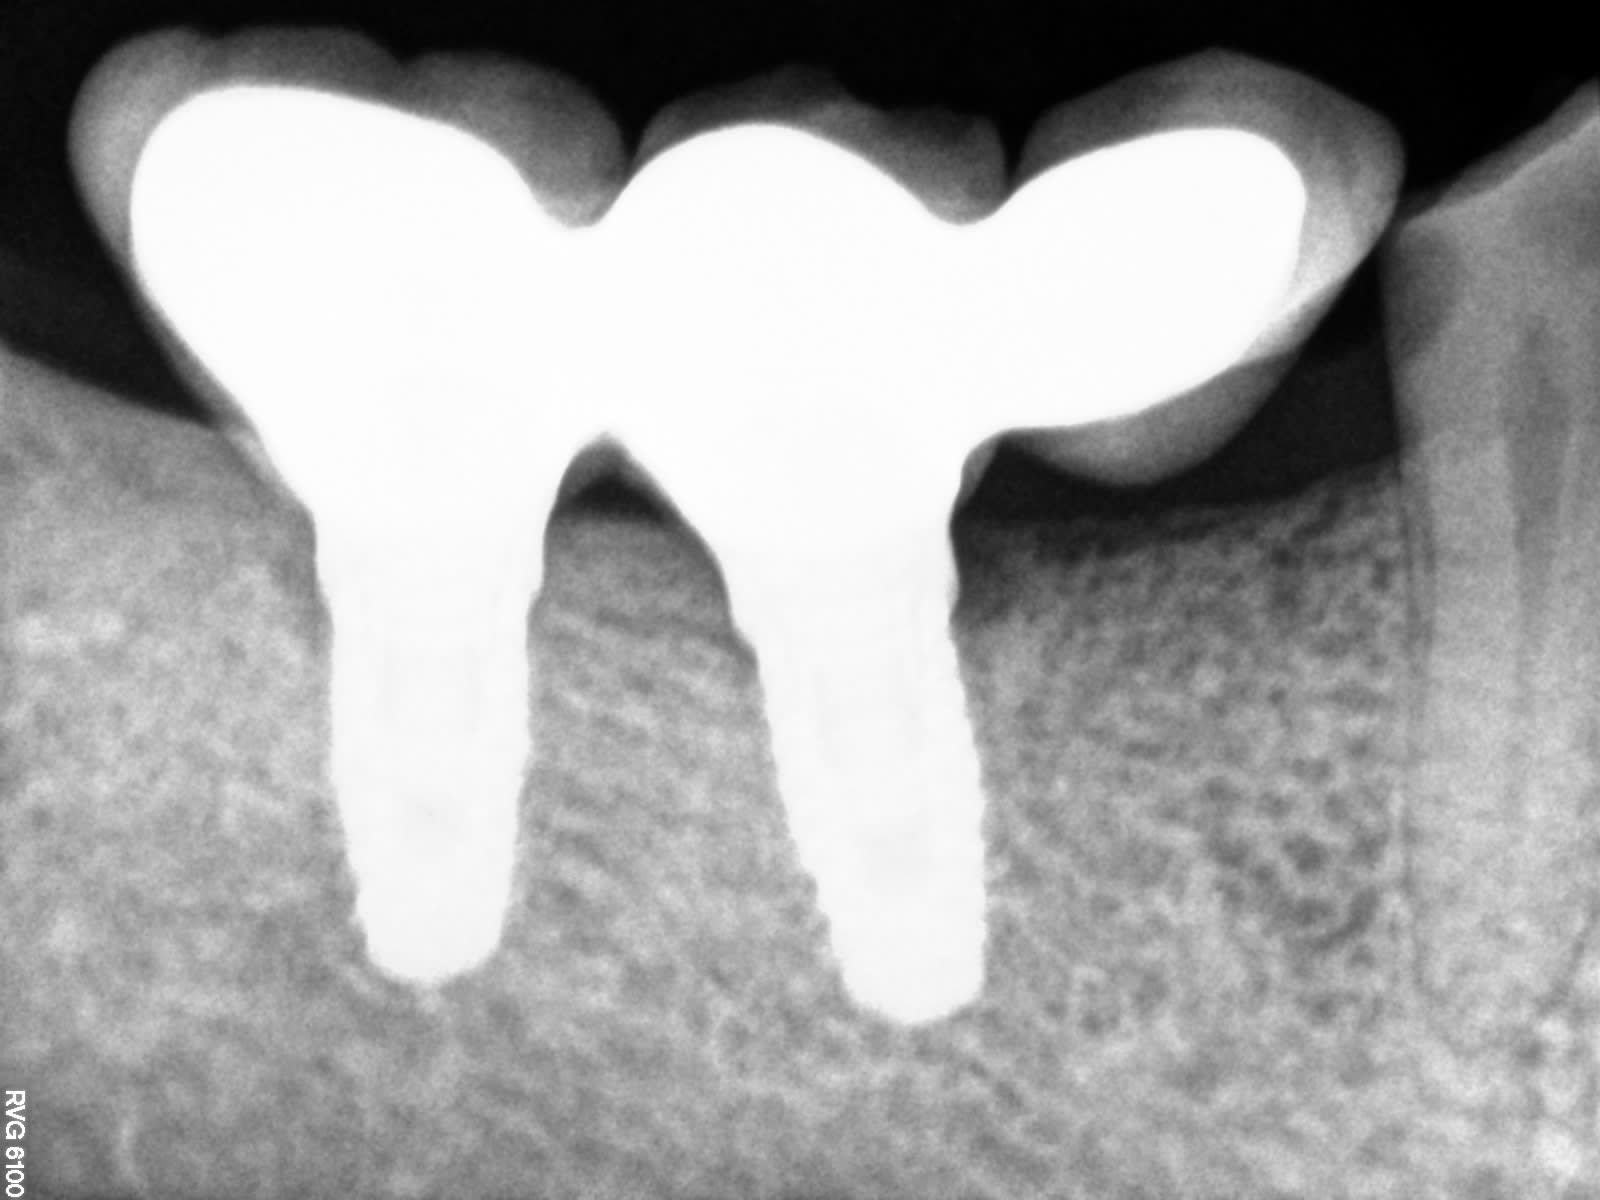

Identification implant

steg

Merci à vous tous pour la grande aide que vous allez sans aucun doute m apporter 😀